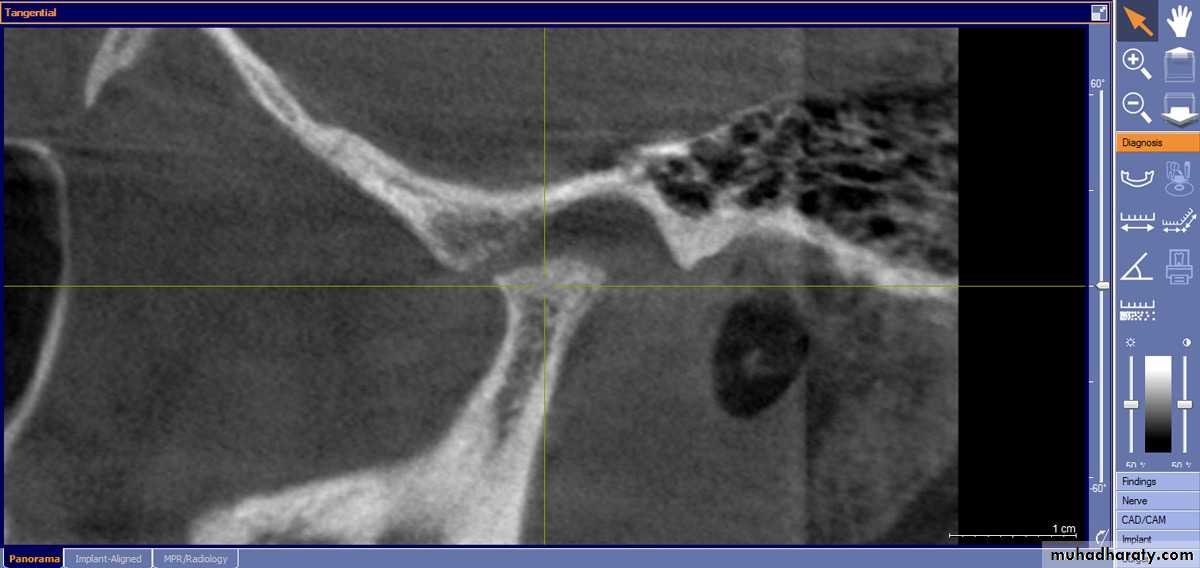

Temporomandibular joint condylar resorption, temporomandibular dysfunction.